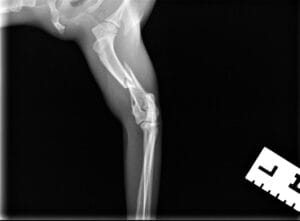

We kregen een oproep over een kitten van ongeveer 5 maand. Ze heeft een ernstige instabiele breuk opgelopen. Wat er is gebeurd, weten we helaas niet. Haar baasje zag wegens persoonlijke redenen verdere behandelingen niet meer zitten en zag geen andere uitweg om voor euthanasie te kiezen. Dit konden wij natuurlijk niet over ons hart krijgen. Na overleg is kleine Filou aan ons afgestaan, zodat zij alle zorgen kan krijgen die ze nodig heeft. Ze heeft een instabiele spiraalfractuur van de humerus aan de linker voorpoot. Filou zal vandaag geopereerd worden en zit ondertussen in een spalkverband dat alles mooi bijeenhoudt. We doen er dus alles aan om haar pootje te herstellen. Dit kost natuurlijk wel wat centjes. Afhankelijk van de complexiteit is de prijsschatting 2500 euro.